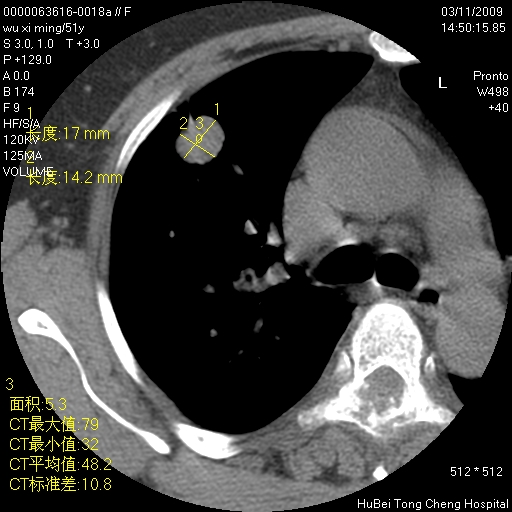

患者 女,51岁。因“胆囊炎,胆囊结石”,行常规术前胸部x线检查发现:右上肺结节病灶,建议行进一步检查。患者无咳嗽、咳痰及咯血等呼吸道症状,近期出现背部疼痛不适。

胸部ct轴位平扫(层厚10mm,螺距1.5,重建间隔10mm;部分层面:层厚3mm,螺距1.0,重建间隔3mm),图像如下:

1、周围型肺癌。(毛刺正、血管束集征,分叶。)

集束征,胸膜牽拉征,毛刺,淺分葉高度提示ca.